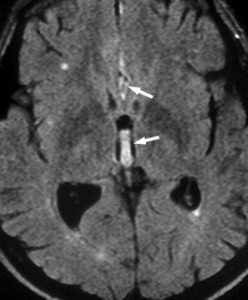

Субарахноидальное кровоизлияние опасно вазоспазмом, который наблюдается на 5-7 сутки. Сам спазм хорошо определяется при дуплексном сканировании. При МРТ головного мозга можно выявить ранние признаки ишемического инсульта.

![вазоспазм при САК]()

МРТ головного мозга. Диффузионно-взвешенная МРТ последовательность. ОНМК в острой стадии вследствие вазоспазма.